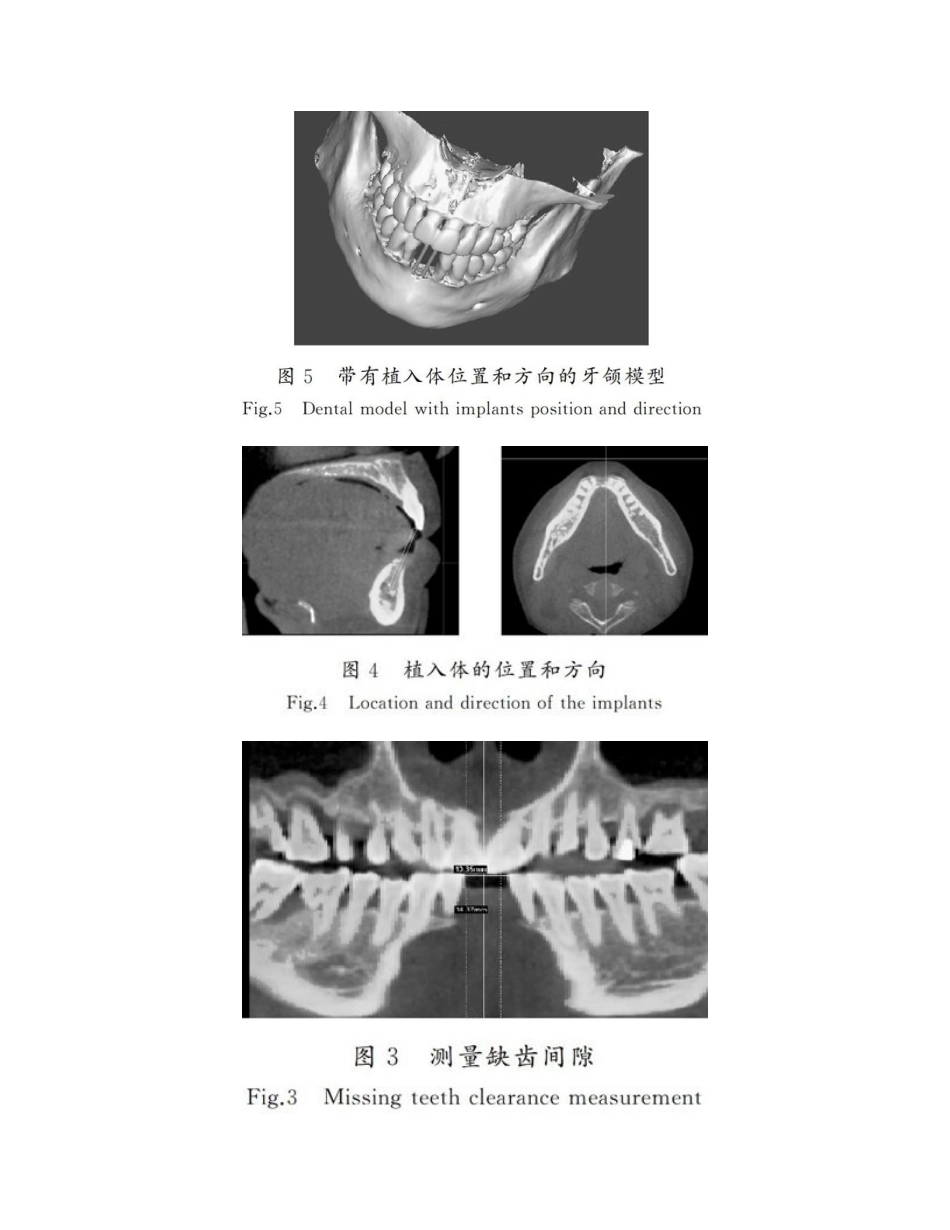

口腔种植导板的数字化设计与3D打印作者:张永弟张子昂杨光张润生来源:《河北工业科技》第04期摘要:为了提高牙齿种植位置和方向的精确性,减少手术难度,缩短手术时间,减少患者术后不适感和并发症等,对承载着种植体抱负植入方位信息的种植导板进行了研究。在没有专用牙齿种植软件的状况下,运用CT图像和三维光学扫描数据重建牙颌模型,使用通用的Mimics,Geomagic和Magics等软件进行种植手术规划与导板设计,并采用FDM和SL两种3D打印工艺对导板进行制作,通过导板与牙模佩戴测试,给出了设计参数,实验成果有助于牙齿种植的数字化和精确化。提出的导板设计与制作工艺能够作为参考,以协助医生和工程师在没有专用的种植软件的状况下,进行数字化导板的设计与制作,提高种植的精确度和成功率。核心词:口腔颌面外科学;口腔种植;种植手术导板;数字化设计;3D打印中图分类号:R782.12文献标志码:Adoi:10.7535/hbgykj.yx04010以修复体为指导的种植技术(prostheticallyguidedimplantology)是根据最后修复体的设计来拟定种植体位置[1],从而确保修复效果,获得最佳的功效和美观。在传统的种植牙手术中,种植体植入的角度和位置依靠医生在术中翻开患者黏骨膜瓣后,根据骨组织状况进行拟定,即便术前借助了影像技术,但术中仍在很大程度上依靠医生的临床经验,这对年轻医生来说存在着很大挑战,影响了种植技术的普及和推广。传统种植手术对于种植体植入位置、角度以及深度存在着相对不可预见性,如果种植体植入位置和方向偏差较大,不仅会影响最后修复体的效果,还可能造成周边重要解剖构造的损伤[2],甚至会引发诸多并发症,如牙槽骨开裂、神经损伤等[3]。第4期张永弟,等:口腔种植导板的数字化设计与3D打印河北工业科技第35卷种植导板是一种承载着种植入体抱负位置、方向、角度等信息的手术辅助装置,是连通术前设计与术中操作的桥梁[2],有助于在手术操作中精确转化术前设计。傳统的种植导板多是在石膏牙模上运用热压膜技术制得[4-6]或采用光聚合托盘材料制得[7]。虽能确保牙冠部分的美观,但还是无法精确控制种植体的三维位置。现在,国外某些公司研发出专用的牙齿种植软件用来进行导板设计,已经商品化的有比利时MaterialiseDental公司的SimPlantPro软件[8]、加拿大Anatomage公司的Invivo软件、瑞典NobelBiocare公司的ProceraTM软件[9]、韩国Cybermed公司的OnDemand3DTM软件、丹麦3Shape公司的ImplantStudioTM软件、美国MediaLabInc公司的Implant3D软件、意大利的3DSENTCAD系统等,但受限于其昂贵的价格而始终未在中国大范畴推广。中国的种植软件有杭州六维齿科的6Ddental软件等。种植软件普通附带种植体库,方便医生选择种植体型号,但现在除了ImplantStudioTM软件设计的导板允许第三方加工外,以上其它公司设计的数据均需要发回原公司制作导板,用时较长。现在,在中国应用区域范畴还比较小,报道仅见于某些规模较大、级别较高的医院,绝大多数的种植手术还仅凭术者经验或仅依靠传统简易种植导板引导手术,因此有必要进一步推动导板设计的数字化,提高导板的制作精确性。近年来,3D打印技术在医学中的应用逐年增多,重要用来制作辅助手术的解剖模型、手术导板和植入物。3D打印手术导板能够缩短手术时间,提高精度,减少辐射,临床效果好,即使耗费稍多某些,但总体成本效益良好[10]。运用3D打印技术,结合3D图像生成及编辑解决软件、逆向三维设计软件等的应用,使得自行设计制作种植导板成为可能。本文重要研究在没有专门牙齿种植软件的状况下,如何运用CT图像、光学扫描、逆向设计和3D打印技术来设计与制作个性化的种植导板,用来辅助医生提高种植的精确度,减少对个人临床经验的依赖,从而助力于种植技术的普及和推广。1种植导板设计种植导板设计时应满足某些原则,如精确地定位和定向、术中固位和稳定性以及不会对周边组织造成不良影响等,但具体设计也要受到患者个体特性以及术中使用的器械等因素的限制。手术导板的设计和制作需要医生和工程师之间的紧密协作,以将治疗需求对的地转移到技术规范中。手术导板有牙齿支撑、黏膜支撑、骨支撑、牙齿与黏膜联合支撑等类型[...